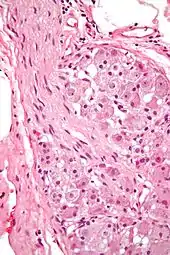

| Ganglion cell | |

| |